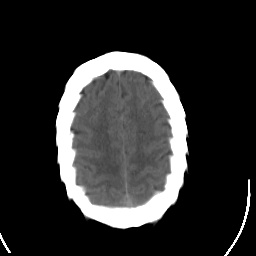

Stroke CT #2 -- Slice #20

[Home][Help][Clinical] Slice 20